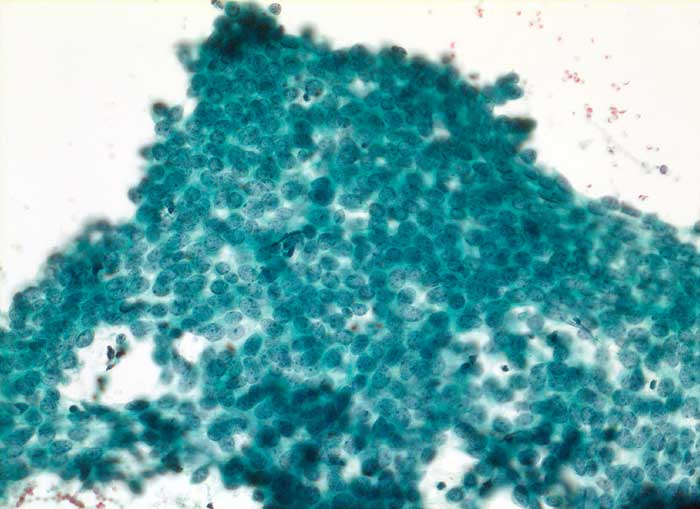

Grosse Mengen epithelialer Zellen, bipolarer Nacktkerne (Myofibroblasten und Fibrozyten) und scharf begrenzte Stromafragmente charakterisieren das Fibroadenom zytologisch. Aspirate von stark fibrosierten Fibroadenomen können auch zellarm sein. Einseitig von Epithel bedeckte Bindegewebsfragmente sprechen für ein Fibroadenom. Durch die Aspiration wird die epitheliale Innenauskleidung mit ihren Verzweigungen aus dem Gangsystem gelöst. Die Epithelverbände sind beim intrakanalikulären Fibroadenom flach und erscheinen beim perikanalikulären Fibroadenom T-, Y-, finger- oder hirschgeweihförmig. Die Kerne sind wenig grösser als die Kerne normaler duktaler Epithelien und messen meist weniger als zwei Erythrozytendurchmesser. Da es sich bei Fibroadenomen um proliferierende Läsionen handelt können die Epithelzellen Zeichen der Aktivierung zeigen in Form einer mässig ausgeprägten Pleomorphie, prominenten Nukleolen, und gelegentlichen Mitosen.

Das erste Beispiel zeigt ein intrakanalikuläres, das zweite Beispiel ein perikanalikuläres Fibroadenom mit stark verzweigten Zellverbänden. Das dritte Beispiel zeigt die Zytomorphologie eines Fibroadenoms mit stark aktivierten Zellen.